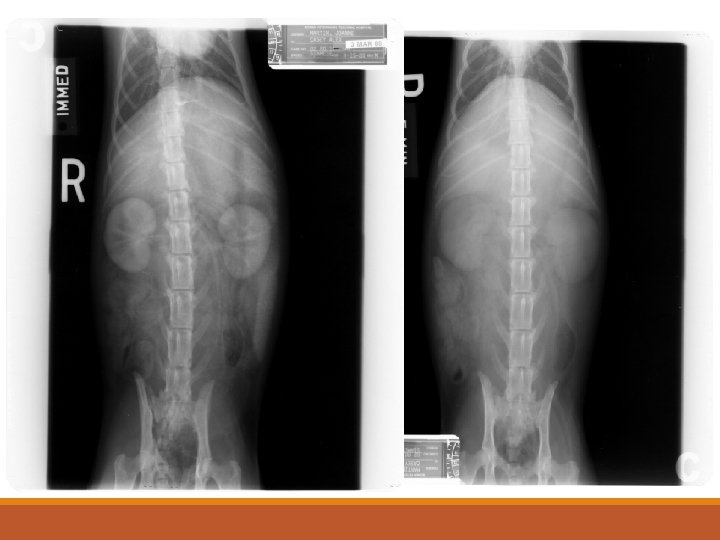

Contrast Studies for the Urinary Tract Excretory Urography (EU) – Intravenous Pyelogram (IVP) – Intravenous Urography (IVU) ◦ Indications ◦ Evaluate kidney morphology – position. Ureters. ◦ Suspected renal disease ◦ Increased radiopacity in the retroperitoneal space ◦ Gross idea of kidney function ◦ Procedure ◦ Preparation required (24 h fasting; enema) ◦ IV access/dose ◦ Radiographic views

Excretory Urography (EU) – Intravenous Pyelogram (cont’d) ◦ Interpretation ◦ Vascular phase Ø 5 – 10 sec ◦ Nephrogram phase Ø 1 – 2 min ØNormal pattern: Initial=Good, then=gradual decrease ØAbnormal patterns: ØPoor – persistent ØPoor – continued increase/ decrease ØGood – continued increase